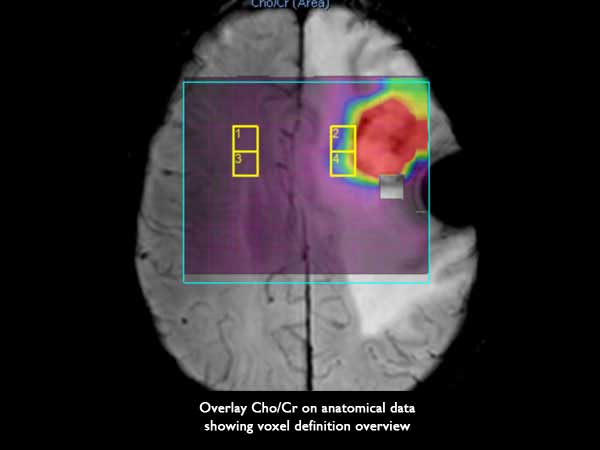

2D PRESS CSI